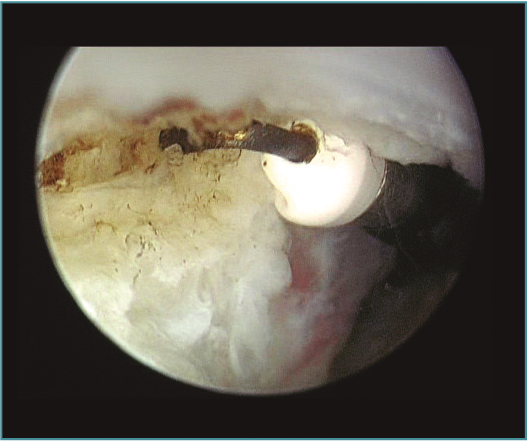

La capsulotomía anterior la iniciaremos de medial a lateral, aproximadamente un centímetro proximal a la punta de la coronoides, utilizando un vaporizador "de gancho" (instrumento que nos parece muy útil para esta tarea, ya que nos permite controlar muy bien la profundidad de la resección de la cápsula para evitar lesionar estructuras neurovasculares próximas); también utilizamos la pinza Basket para resecar la cápsula, sobre todo en los casos en los que está muy engrosada y endurecida (Figura 7). Para disminuir el riesgo de lesión del nervio interóseo posterior (que queda cerca de la cápsula anterior al nivel de la cabeza del radio), dejamos intacta o parcialmente resecada la cápsula sobre la cabeza radial y completamos la capsulotomía con una extensión forzada del codo. Una vez hemos completado la capsulotomía anterior, veremos el tejido muscular del músculo braquial (Figura 8). En este momento no es recomendable resecar más hueso o tejidos blandos por diferentes motivos: al no tener la protección de la cápsula anterior, las estructuras vasculonerviosas están en mayor riesgo de lesionarse; además, en los casos de rigidez el músculo braquial puede ser más delgado, debido a atrofia muscular(14). Otro motivo es evitar el sangrado del músculo, para disminuir el riesgo de aparición de calcificaciones heterotópicas. En caso de ser necesario resecar hueso tras la capsulotomía, emplearíamos un separador a través de un portal anterolateral accesorio y el sinoviotomo o la fresa sin aspirador conectado (Vídeo, minutos 1:36-2:46).

Figura 7. Visión artroscópica desde el portal anteromedial de la realización de una capsulotomía anterior del codo. Vemos la cabeza del radio en la parte más lateral y el músculo braquial en la parte más medial. Apreciamos el grosor de la cápsula anterior en este caso de rigidez postraumática.